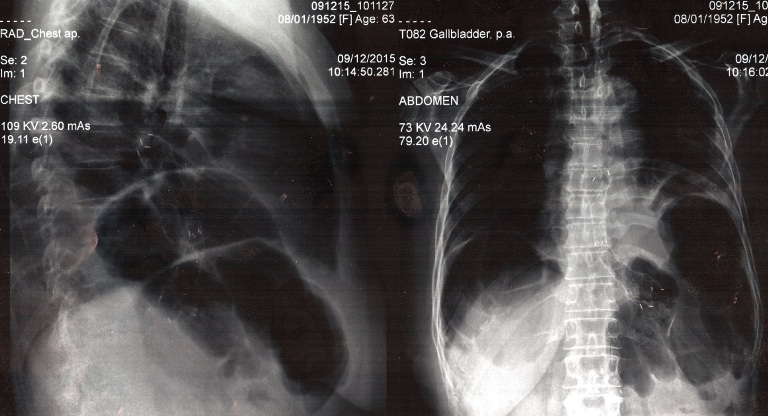

Radiografia de control de la 9 decembrie a indicat: Rezultat bun. Contrastarea cu soluţie de contrast solubilă cu tranzit respectat prin esofag şi stent, fără fistulă.